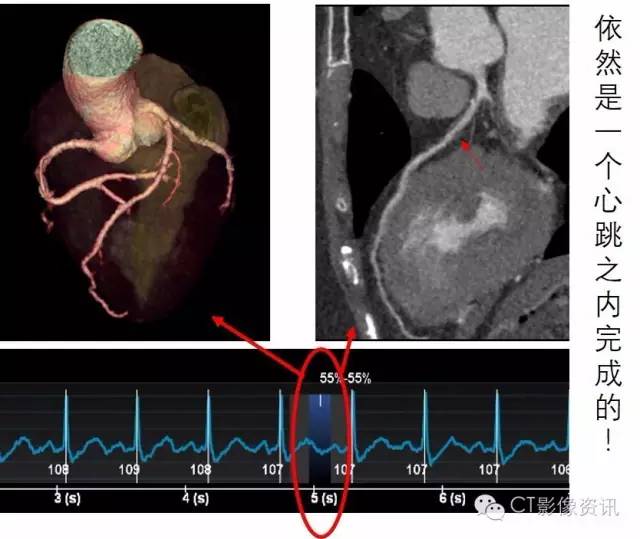

高心率的可以一个心跳扫描完成,那心率不齐,房颤的,以往设备都做不好的能行不?您看,房颤的患者来了!

您看看这心跳的节律,一会儿53,一会儿116,让扫描老师咋办?这种极不规则的心率对常规的设备就是一场惊心动魄的挑战!假如扫描时落在低心率时,成功率比较高;假如扫描时落在高心率时,有可能不成功,假如扫描时不幸落在正在活跃的R波上,那就可能导致重做的风险!假如……,噢,现在不用假如了,我用Revolution CT就行了!

武汉大学人民医院于11月刚装机的世界顶级CT—Revolution CT实现了影像同仁十多年的夙愿!最大16cm宽度探测器的超大体型能够一次曝光就覆盖完成11~14cm的心脏范围;业界最好的29ms 3D时间分辨率可以像抓拍百米冲刺的运动员那样冻结住极度不规则心律的心脏!高超过硬的技术含量,让所有的冠脉CTA都在一个心跳之中完成!您知道这意味着什么吗!就在您刚要一吸气的时候,您的冠脉CTA已经检查完了!连屏气都省啦!

同样的这样的检查在探测器宽度不够宽的设备上需要多个心跳才能完成。而每多一个心跳的曝光,就意味着更多的辐射剂量,现在咱们的Revolution CT可以直接像做体检一样进行!One Beat不再是一个目标,是每天常规进行的检查!